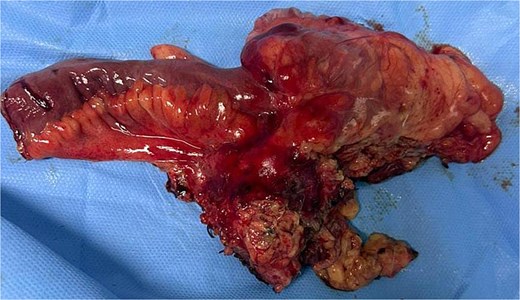

A 29-year-old patient with no significant medical history presented with right iliac fossa pain associated with diarrhea for 4 years, evolving in a context of preserved general condition. Clinical examination revealed tenderness in the right iliac fossa with a good overall state. The biological assessment was normal. The patient underwent a total colonoscopy, which identified non-specific interstitial colitis. An abdominal computed tomography scan was then performed, suggesting an intraperitoneal mass located in the right iliac fossa, containing calcifications and measuring 37 × 49 mm (Fig. 1). The biopsies were non-contributory. The patient was operated on, and surgical exploration revealed the presence of a small intestine tumor invading the base of the cecum. An ileocecal resection was performed (Fig. 2). Histological examination showed a tumor proliferation of fibroblastic nature with variable cellular density, including areas of hypocellular fibrous collagen. There was also an associated lymphocytic inflammatory infiltrate and calcifications. To rule out the diagnosis of gastrointestinal stromal tumors, the main differential diagnosis, immunostaining with anti-CD117 antibody was conducted. The tumor did not express this antigen. The diagnosis of calcifying fibrous tumor was retained.

Intraperitoneal mass located in the right iliac fossa, containing calcifications.